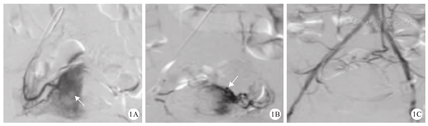

介入组孕妇DSA影像表现为,双侧子宫动脉明显增粗、扭曲紊乱、外展及上移,呈横行卷曲绒线状。其中8例合并阴道出血者,在动脉期可见造影剂浓染,呈小雪花片状影,边缘模糊(图1A、图1B),胎盘血供丰富,中央性前置胎盘孕妇的胎盘附着于子宫下部,部分性前置胎盘孕妇的胎盘附着于子宫侧部。子宫动脉远端栓塞后,子宫动脉出血停止,浓染的造影剂消失(图1C)。孕妇子宫动脉栓塞术DSA影像结果,见图1。